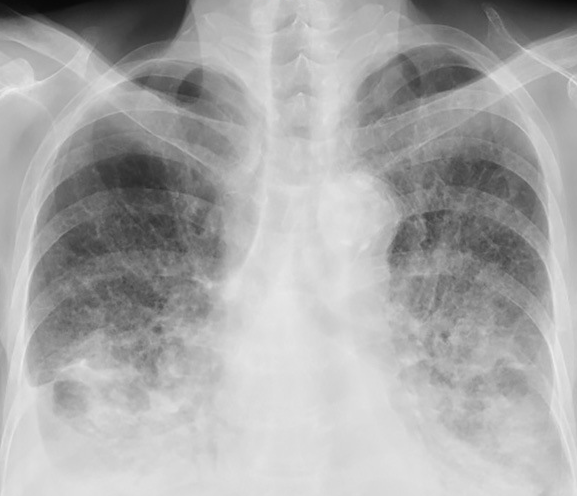

Αριστερός ημιθώρακας μεγαλύτερος από τον δεξιό (Ευγενική παραχώρηση Dr. V. Penopoulos)